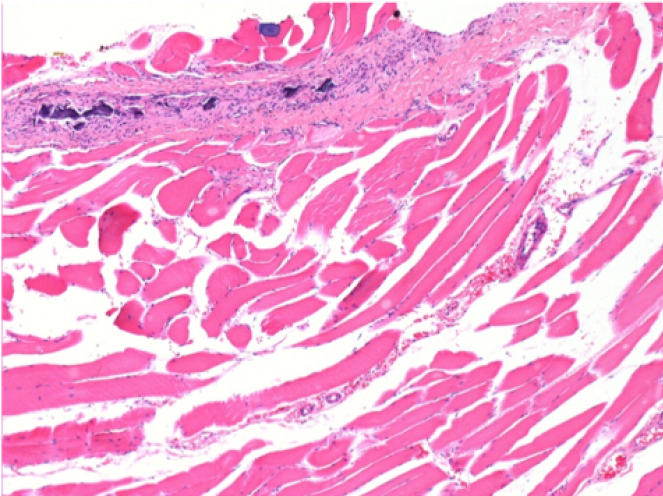

10 days after Endopeel Injection 0.1ml in the right pretibial muscle.

Here you may see the formation of the vacuoles which are surrounded by lymphocytes. Vacuoles are different from tissue necrosis . The presence of lymphocytes is related to the permeability of the cell membranes.